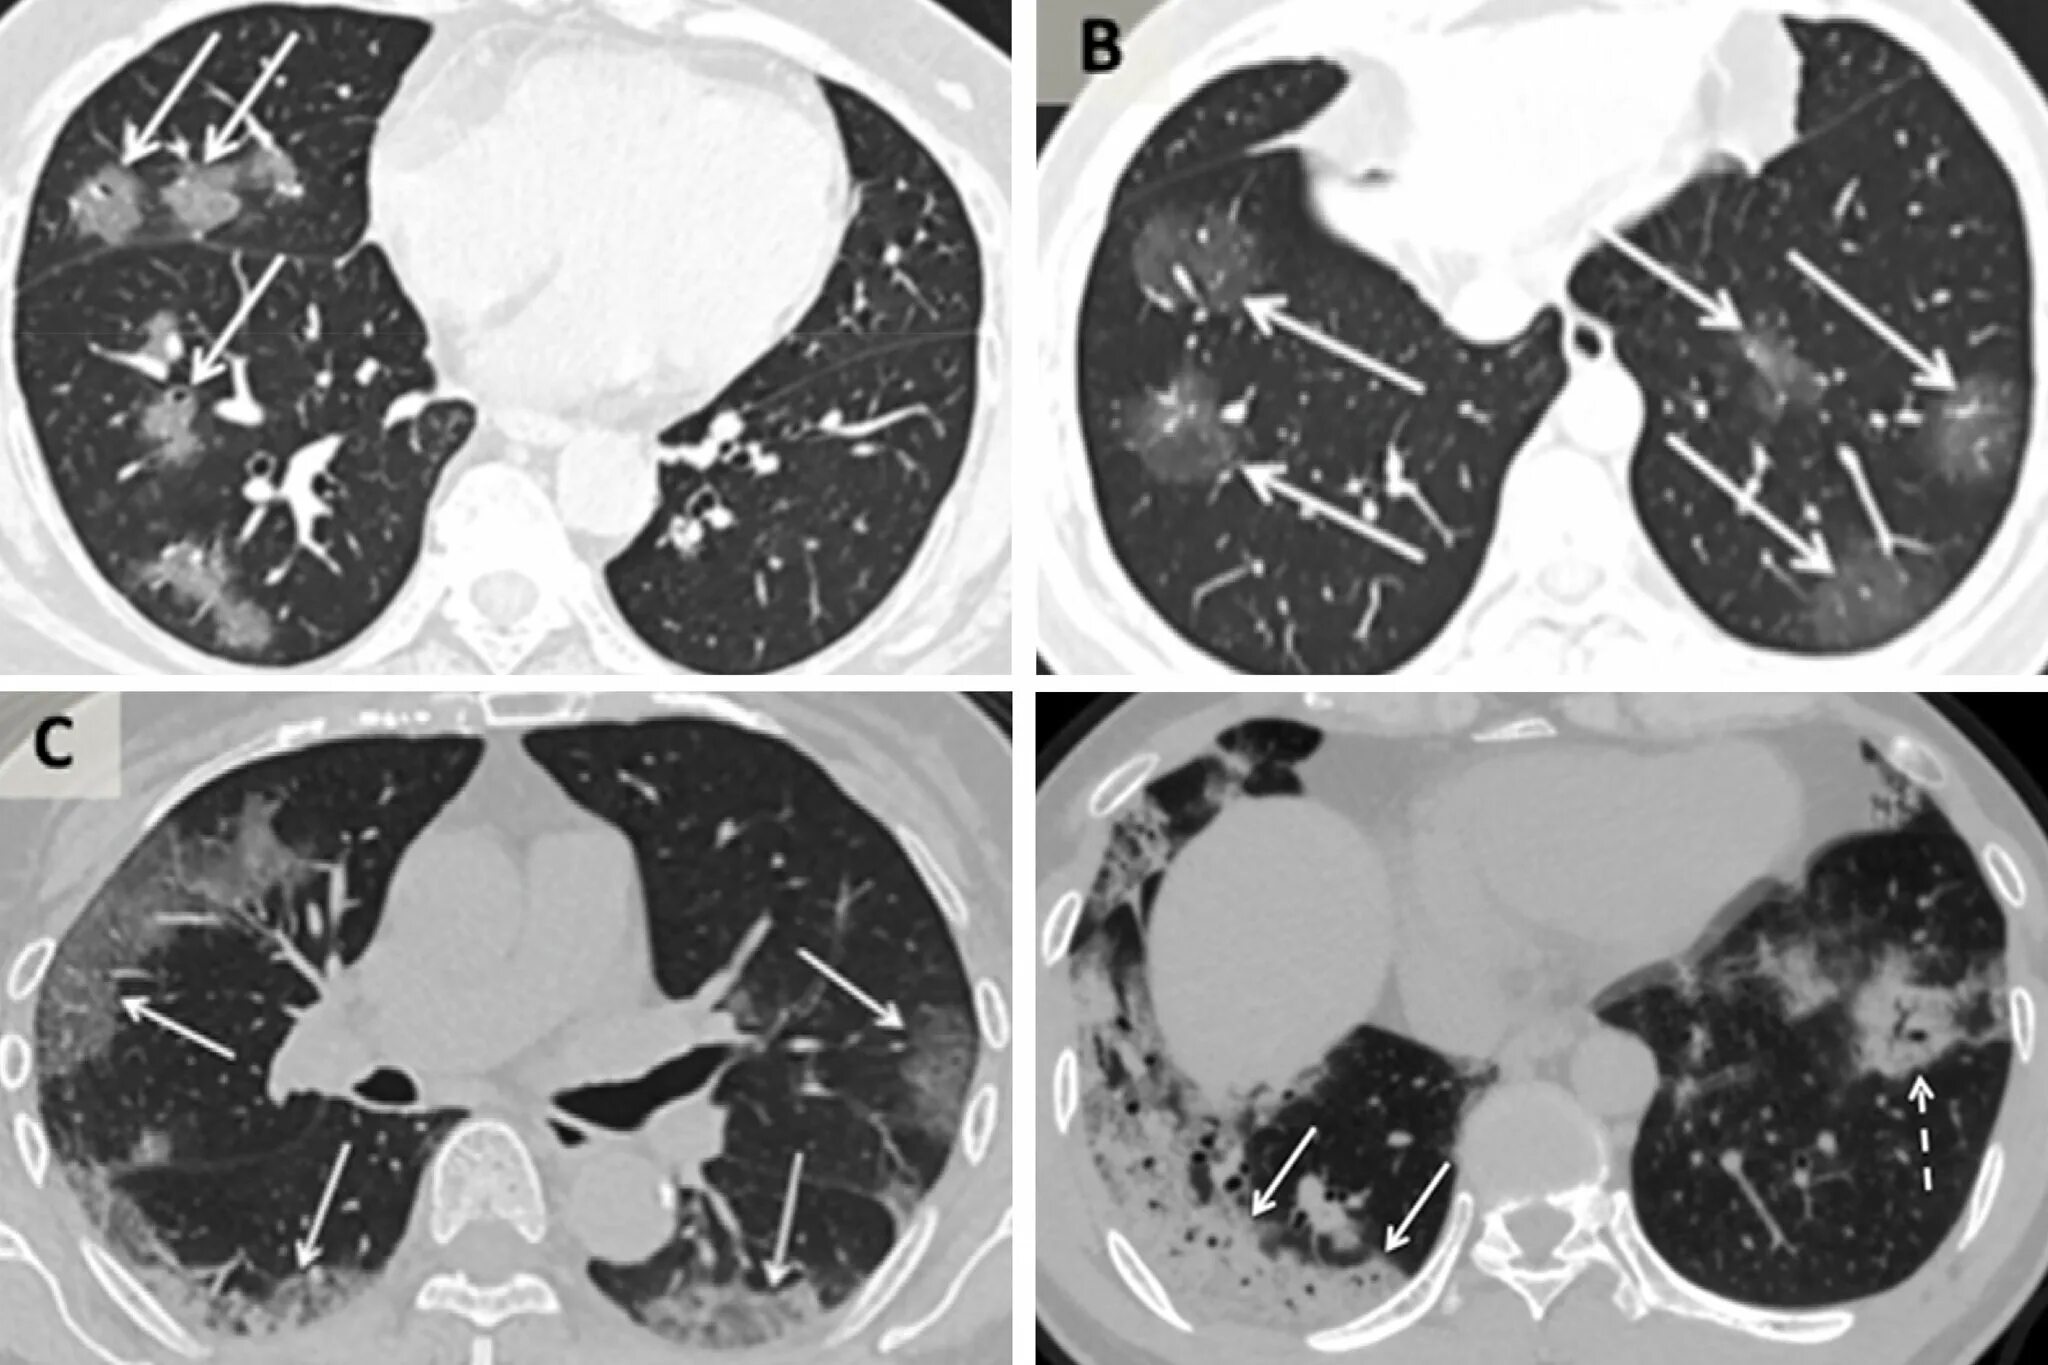

Болит кт